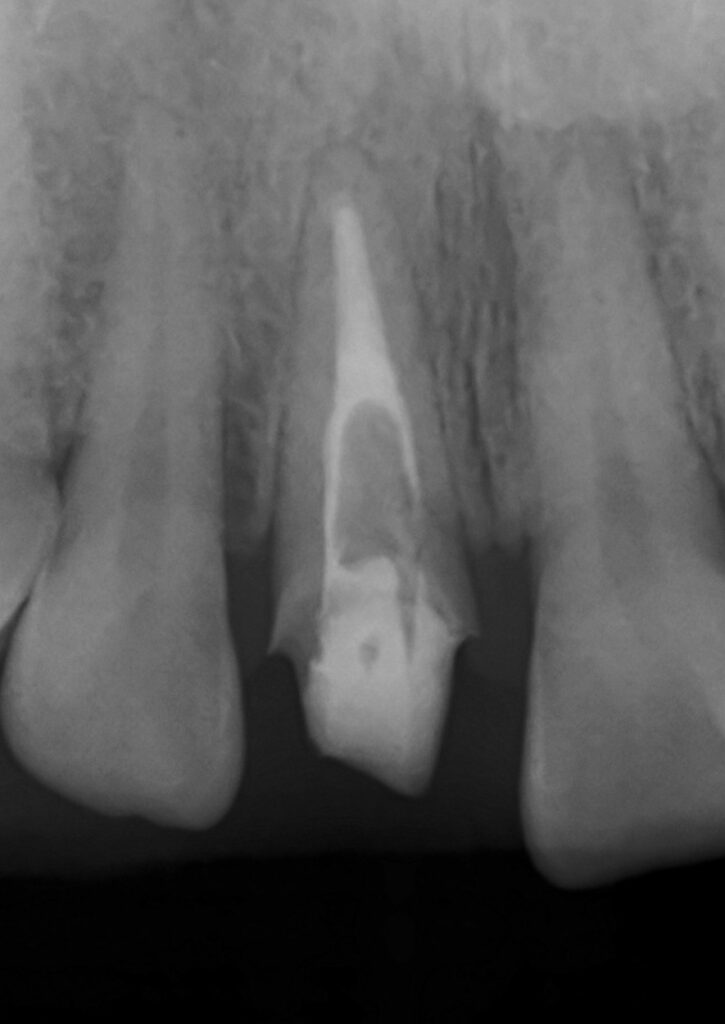

その後当院で根管治療をやり直したエックス線写真です。

歯の根の中に白いお薬が、根の先端に向けて入っているのが見えます。

もちろんスクリューピンも取り除きました。

これが本来ちゃんと神経治療を行なった歯の状態です。